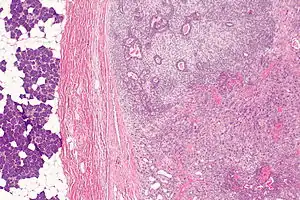

| Micrograph of a carcinoma ex pleomorphic adenoma. The carcinoma component is on the lower right of the image. Benign parotid gland is seen at the left and pleomorphic adenoma is seen at the upper right. H&E stain. | |

Carcinoma ex pleomorphic adenoma is diagnosed by examining it under the microscope with consideration of the individual history.